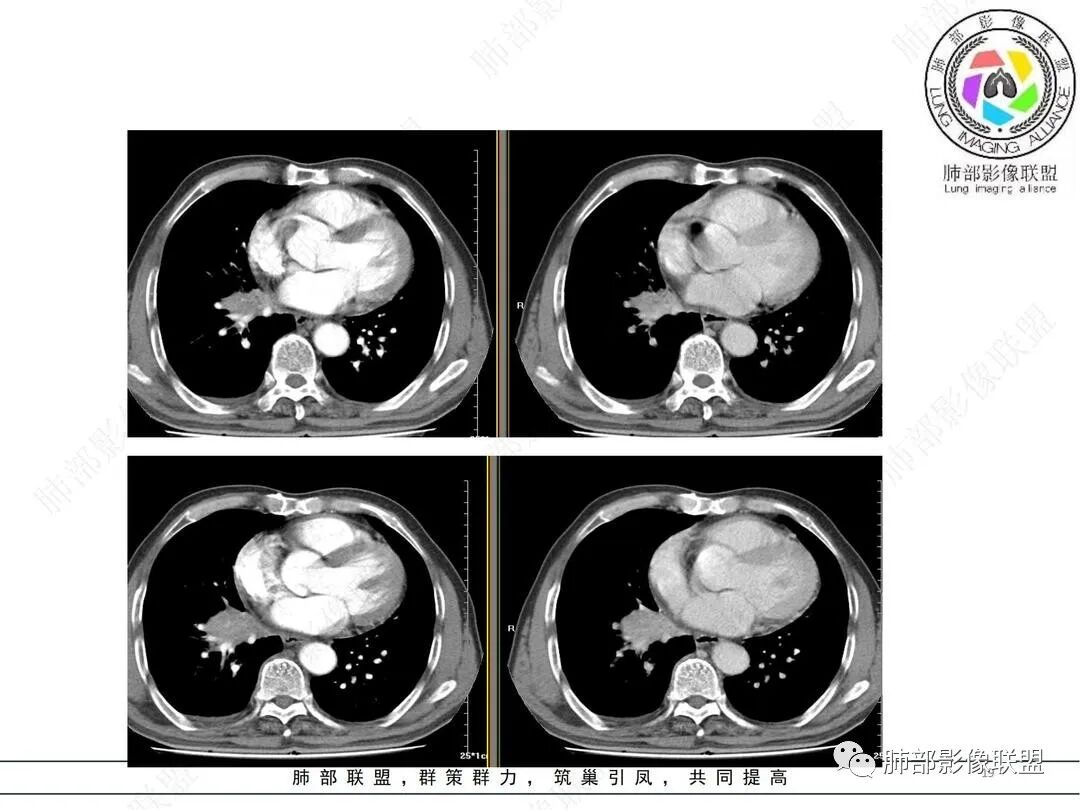

临床考虑肺结核,抗结核后3个月复查病灶明显缩小

邓文睿:这个中间还有一次复查,是部分吸收,我没放图,后面是全部吸收了。

两肺下叶背段都有病灶,可能大家忽略了。第二次复查的时候明显缩小,但是支气管还是没通,没敢除外肿瘤。第三次才全部吸收。这里放的是最后一次复查,已经完全吸收,中途还有一次复查部分吸收没放上来。

(1)病灶形态和分布:双肺散在点片影,可见树芽征。右肺下叶内基底段实性密度团块状影,底部坐落膈面、浅分叶,略呈圆锥形沿血管支气管束探及肺门,可疑“支气管爬行征”。奇食窝区分出子灶。病灶轻中度强化不均,斑片状低密度无强化区,疑坏死,未见钙化。右肺门及淋巴结肿大。

(2)支气管和血管:右肺支气管分支管壁弥漫性增厚,中间段支气管散在结节样凸起,右肺下叶内基底段支气管闭塞,但远端可疑复出。余病灶围绕支气管腔内远端无明显阻塞性不张。内部血管走形自然,提示包绕为主。

综上:病灶形态与肺段契合,血管穿行自如,更符合炎性病变,支气管腔内改变等,结核有待排除。存在支气管腔内改变,尤须支气管镜探查。

支气管闭塞及坏死应想到肺鳞癌,但旁若无人的穿行血管让人疑惑,同样也较少见于破坏性较强的肺结核。病灶周边形态及强化特点等似乎不大支持腺癌。小细胞癌则似乎与肺门纵隔淋巴结肿大程度不相称。

就病理而言,对存在结核不持异议,但短期内吸收太彻底,病灶主体应更多为普通炎性浸润。